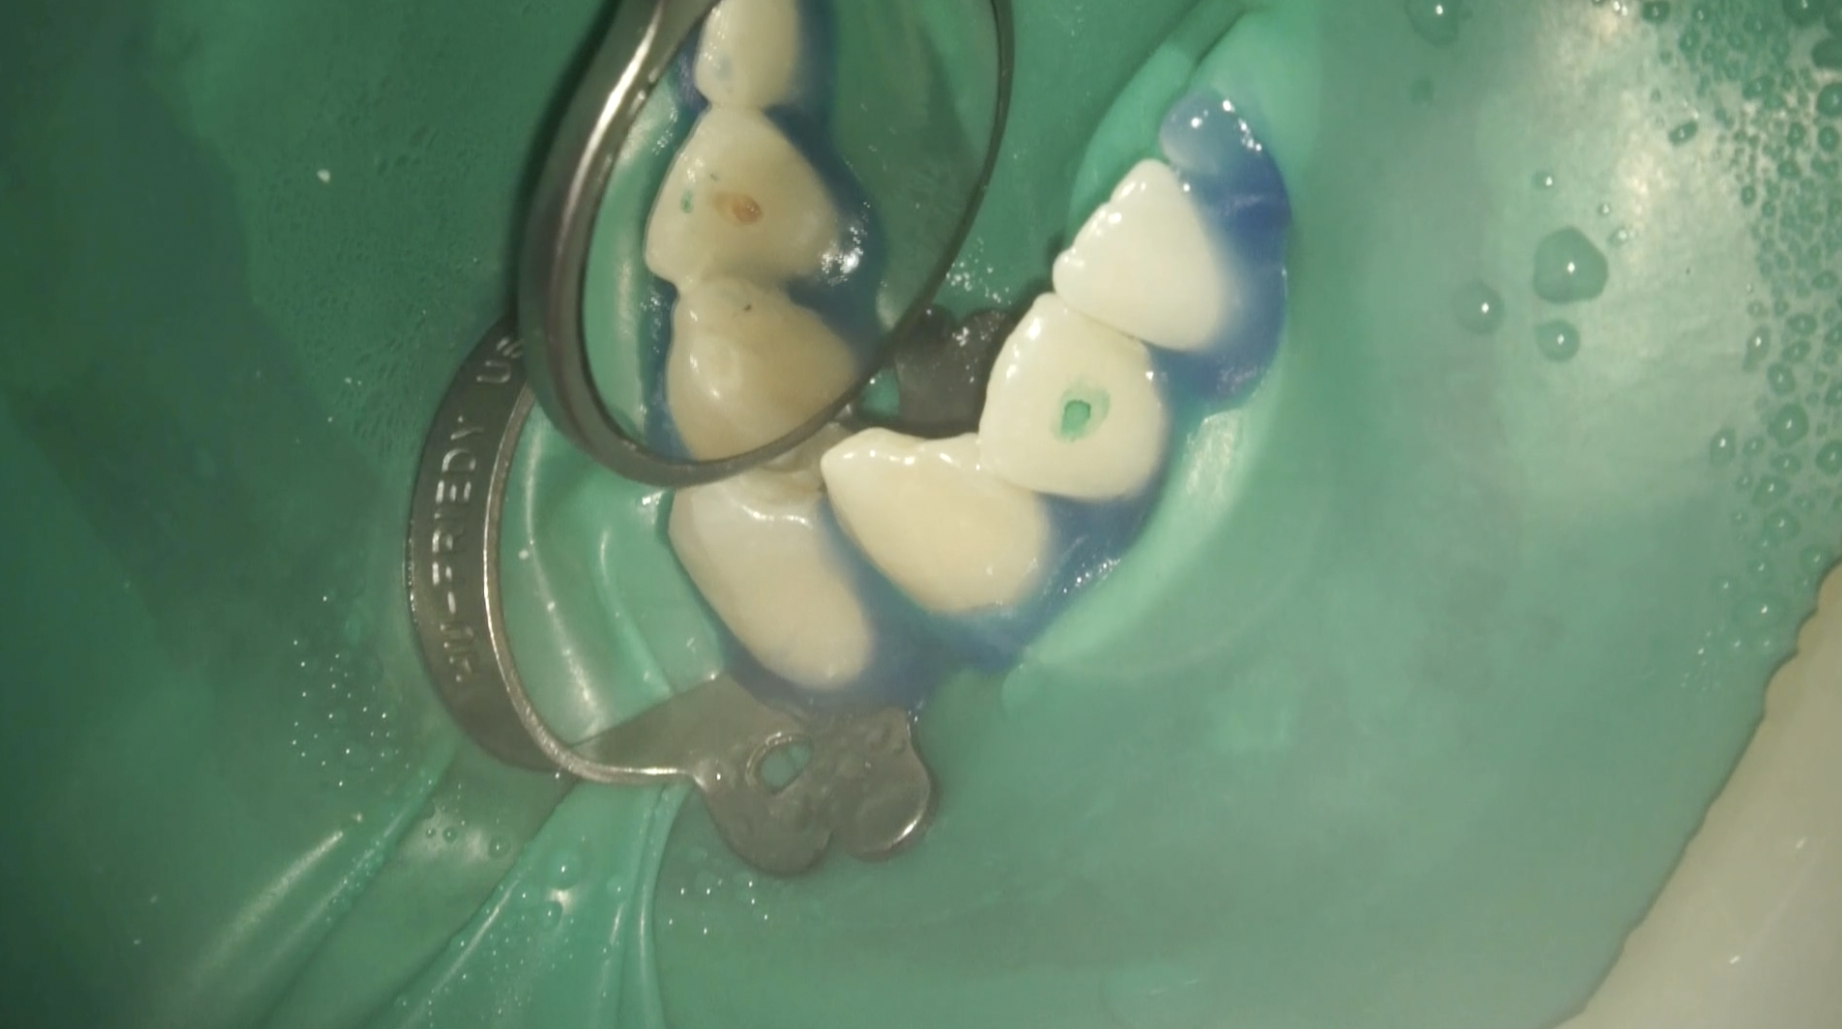

#26 RCT(2025.4.16)

緑のマジックの最下部がチャンバーオープンするべき位置であろう。

先端が細いバーで削合した。

深さは約2mmだ。